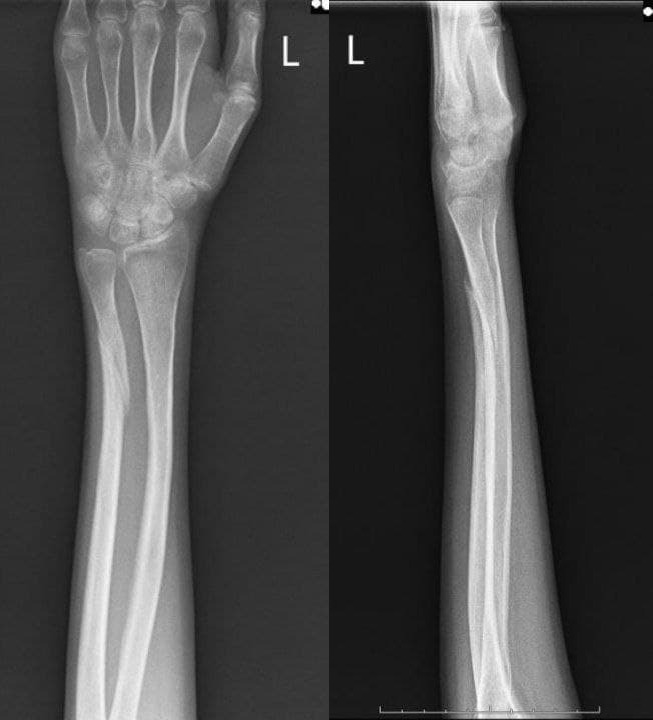

Рентгеновский снимок предплечья в гипсе в день первой встречи - виден перелом локтевой кости.

Рентген контроль сращения через 8 недель - видны признаки замедленной консолидации, допустимое угловое смещение отломков.

Рентген контроль сращения через 12 недель - признаки консолидирующегося перелома локтевой кости.